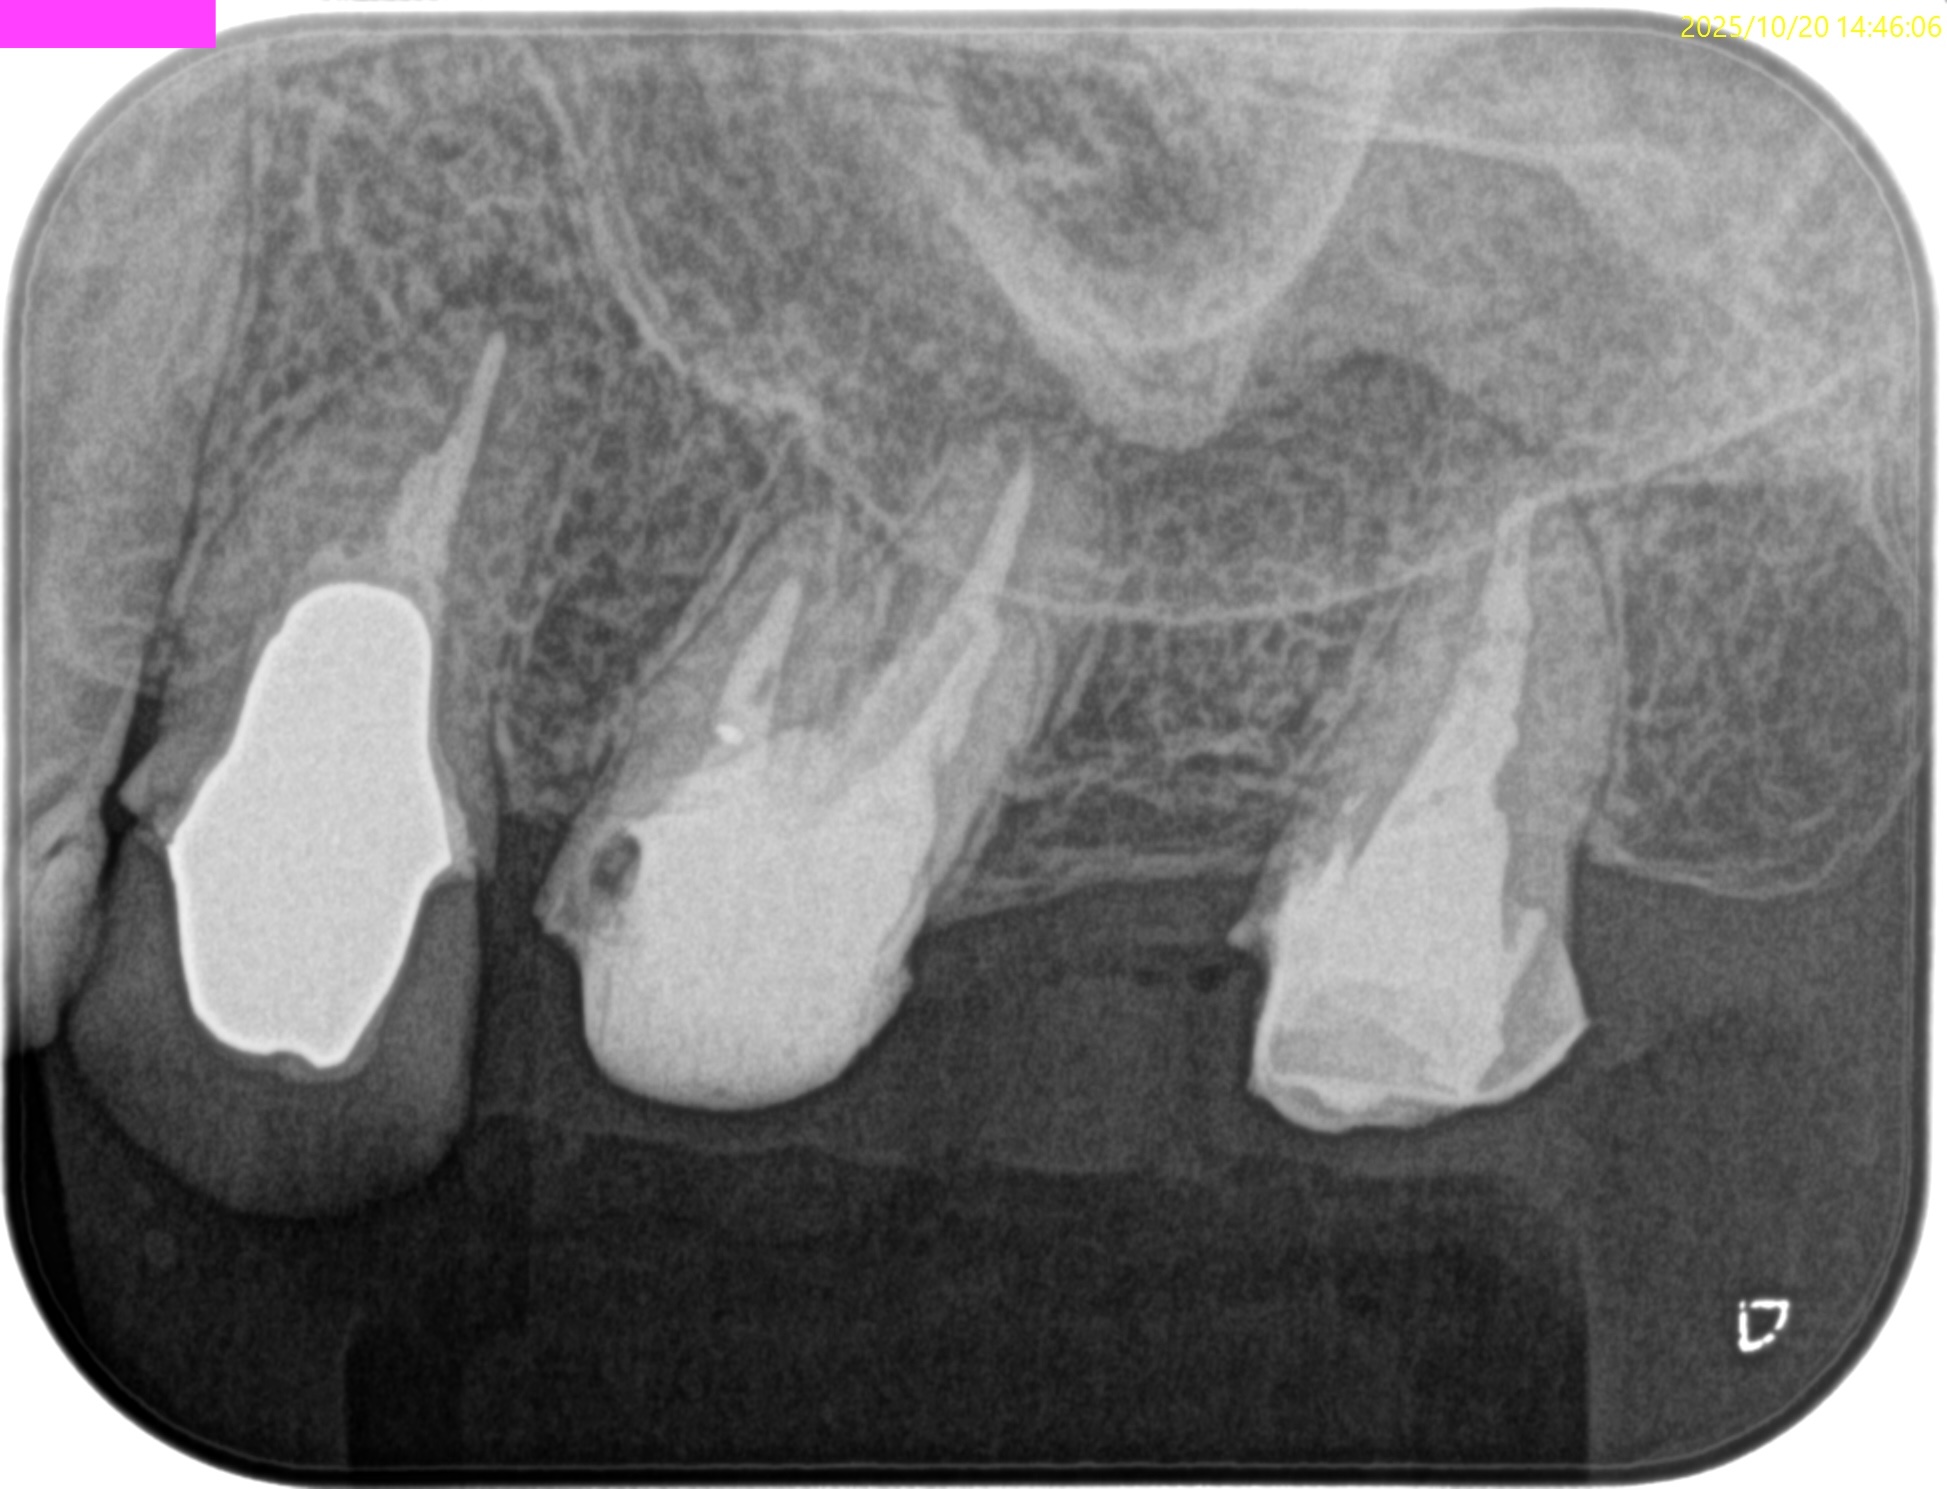

術後にPA, CBCTを撮影した。

#3

MB

DB

P

#14

#16

再治療では3根管とも#25.VがいきなりReference Pointに到達したことから#60.02まで形成した。

#3 作業長 #14 作業長 #16 作業長#3,14は#60.02まで、

#16に至っては根管形成自体ができていない。洗浄のみで再根管治療が終了している。気休めに超音波洗浄しただけだ。